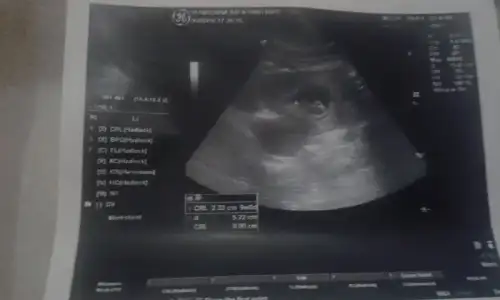

Işte minnak bebişim teyzoslari büyümüşmü :KK68:

Eklentiler

• 1454777641458789206803.webp

1454777641458789206803.webp

10,1 KB · Görüntüleme: 104